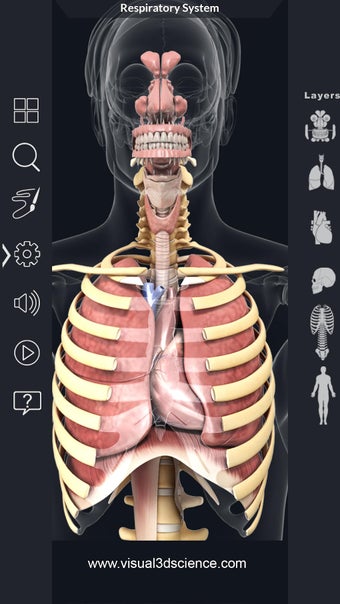

呼吸器系の解剖学は、肺、気管、およびすべての気道を含む呼吸器系の解剖学の研究です。最も一般的なアプローチは、系を上部と下部に分割することです。上部には気管、主気管支、および終末および前頸気道が含まれます。下部には肺と最小の大きさの末梢気道が含まれます。これらの部分それぞれには特徴的な外観と機能があります。

このアプリケーションは、高度にリアルな呼吸器系のモデルです。ユーザーは任意の角度および任意の平面から呼吸器系の解剖学を表示できます。ユーザーは360°回転し、ズームインおよびズームアウトして解剖学をよりよく研究することができます。ユーザーはまた、画面に描画するためのさまざまなツールを使用して写真を撮ることもできます。